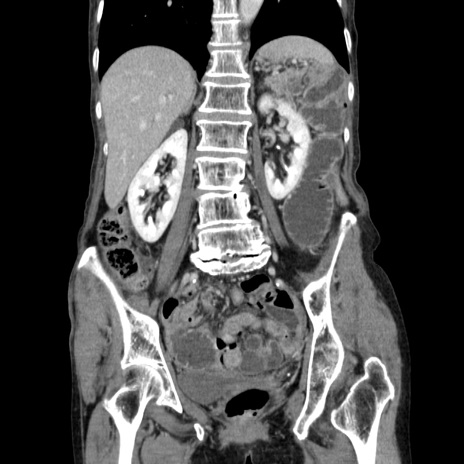

症例25(冠状断像)

【症例】80歳代女性

【主訴】胸のつかえ感

【現病歴】約9時間前に食後から胸のつかえた感じあり、嘔吐あり、来院。

【既往歴】胃癌(全摘)、胆摘、虫垂炎

【身体所見】心窩部に圧痛あり、反跳痛なし。

【データ】WBC 5700、CRP 0.05